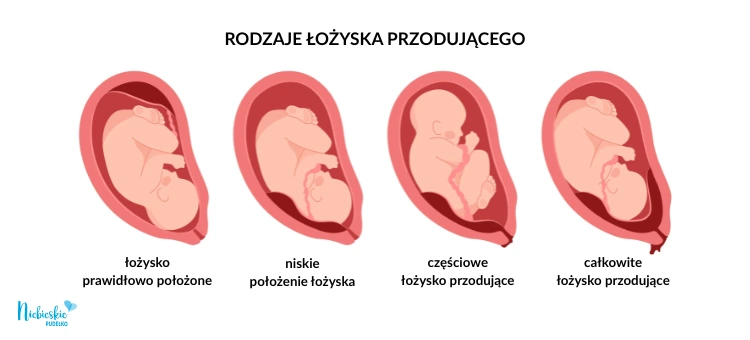

Łożysko przodujące to nieprawidłowe położenie łożyska w macicy, w którym organ ten znajduje się nisko i częściowo lub całkowicie zasłania ujście wewnętrzne szyjki macicy. W prawidłowej ciąży łożysko umiejscawia się w górnej części macicy, natomiast w przypadku placenta praevia może utrudniać lub uniemożliwiać poród drogami natury. Taka lokalizacja zwiększa ryzyko krwawień w czasie ciąży i porodu, dlatego wymaga szczególnej kontroli lekarskiej i regularnych badań USG.

Poza oczywistym problemem przesłonięcia płodowi drogi wyjścia, łożysko przodujące może zmniejszać szansę na pomyślne donoszenie ciąży. Dużo w tym zakresie zależy od stopnia, w jakim organ zachodzi na szyjkę macicy. Mówi się bowiem o pełnym zakryciu, częściowym oraz marginalnym – to pierwsze stwarza oczywiście najwięcej powodów do niepokoju.